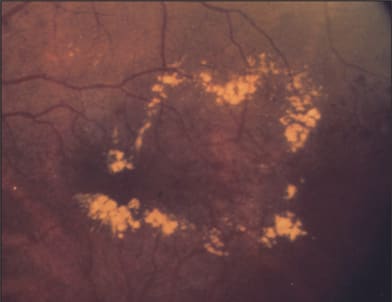

The management of diabetic retinopathy remains a challenge. Diabetic macular edema (Figure 1) is a major cause of vision loss. The Early Treatment of Diabetic Retinopathy Study (ETDRS) showed a 50% reduction in the risk of moderate vision loss (15 or more letters) at three years with focal laser photocoagulation.1 However, only 16% of patients with a baseline vision of 20/40 or worse improved by 15 letters at three years. The low rate of visual improvement has fueled interest in other treatment modalities.

Figure 1. Diabetic macular edema.